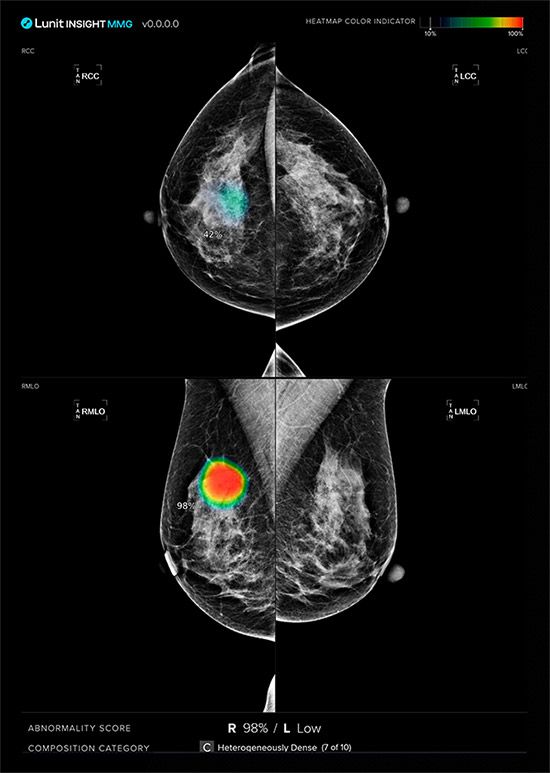

사측은 해당 프로젝트의 전체 3단계 중 1단계에서 약 65만 건의 유방촬영 영상을 AI 영상분석 솔루션 ‘루닛 인사이트 MMG’로 분석해 기술의 정확성과 신뢰성을 입증했으며, 이번 2단계에서 검진 데이터 약 20만 건을 활용해 내년 6월까지 약 6개월 간 추가 검증을 진행한다고 설명했다.

2단계는 실제 설치에 앞서 루닛 솔루션의 최적화 및 유효성 검증 작업(Prospective Validation)을 진행하며, 이 과정에서 최근 미국 식품의약국(FDA)의 승인을 받은 3차원 유방단층촬영술 AI 영상분석 솔루션 ‘루닛 인사이트 DBT’에 대한 평가 작업도 진행될 예정이다. 이후 마지막 3단계에서는 BSNSW 의료진이 루닛 인사이트 MMG를 활용해 검진을 수행할 예정이다.